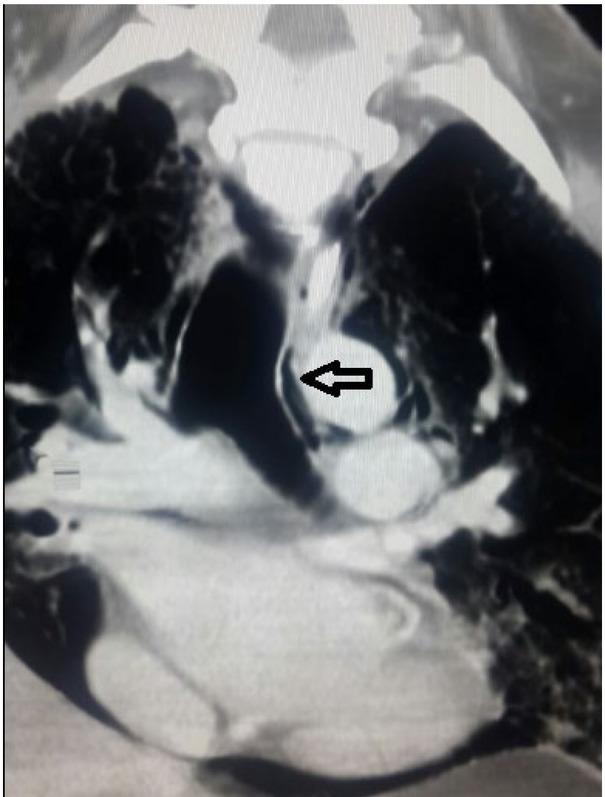

A coronal plane CT thorax showing extensive pneumomediastinum with peribronchial air (arrow) demonstrating the Macklin effect. Also we can see the continuous diaphragmatic sign.

A commonly accepted mechanism is termed the Macklin phenomenon which suggests that coughing increases intra-alveolar pressure, causing alveolar rupture subsequent to which air tracks along the peribronchial and perivascular sheaths due to a pressure gradient between the mediastinum and subcutaneous tissue [5]. Alveolar rupture is usually precipitated by excessive coughing or the Valsalva manoeuvre due to barotrauma [6].